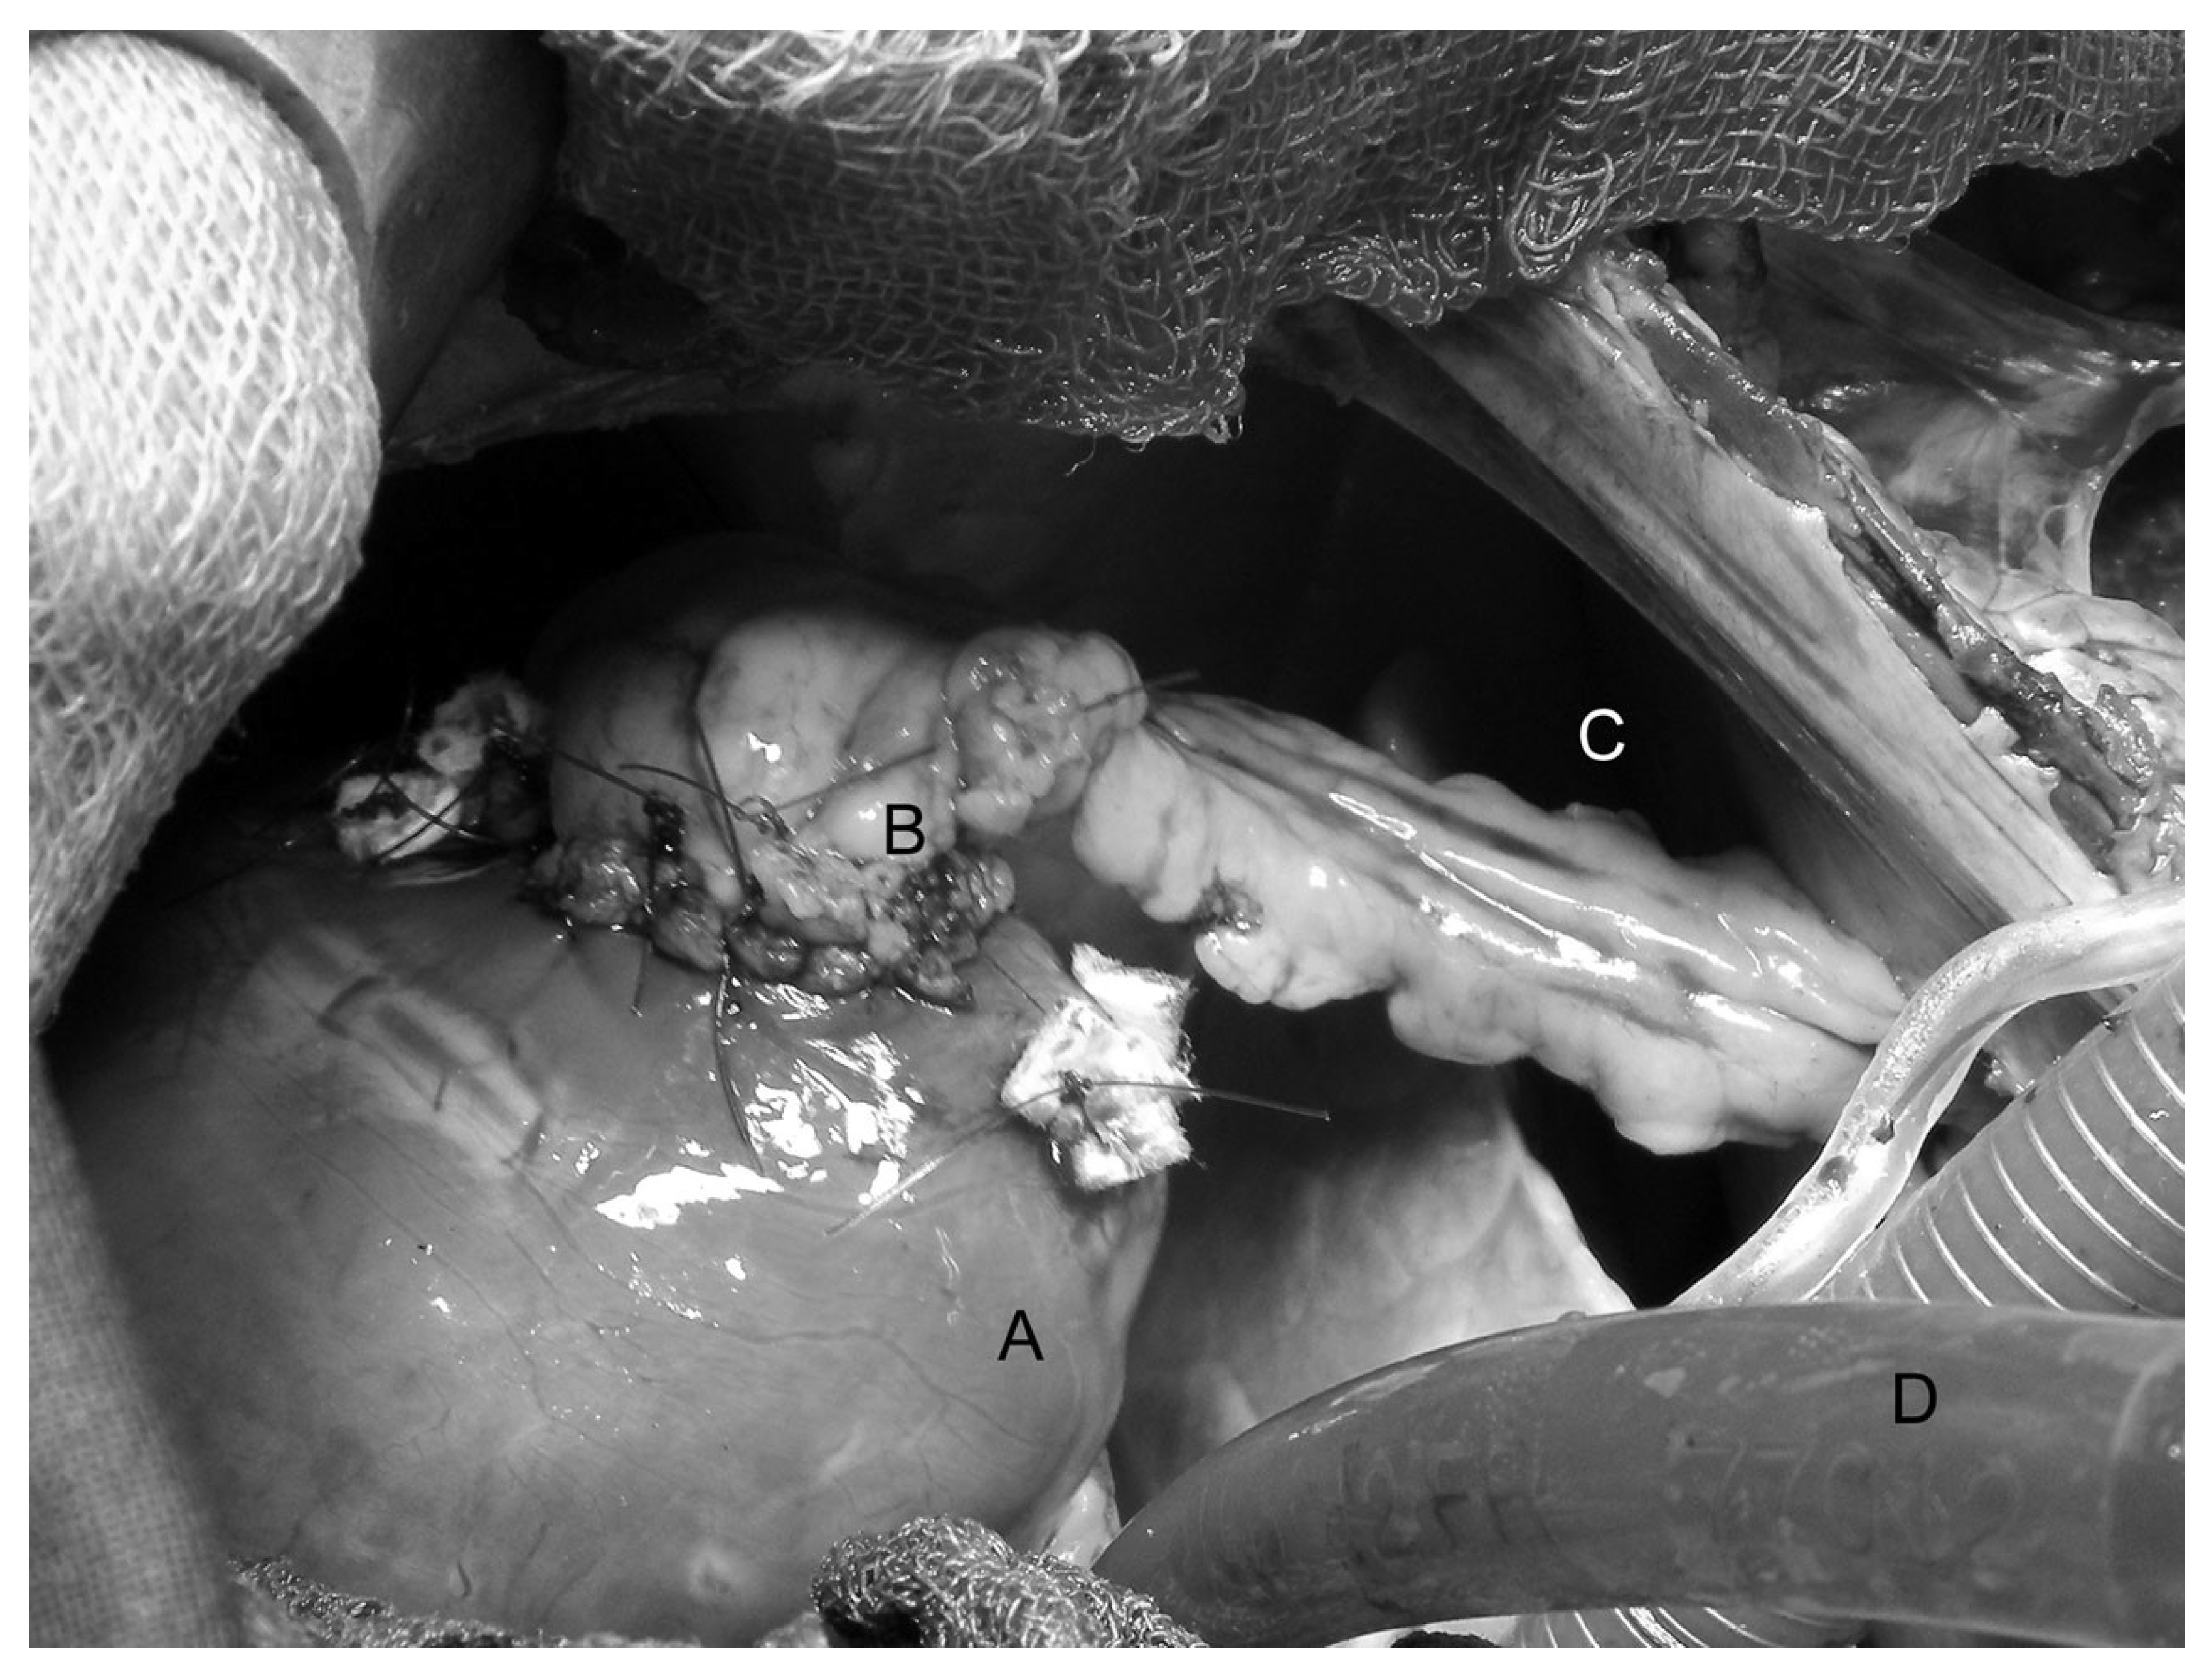

Figure 2.

Intraoperative situs showing the implantation of a vascularized stomach segment in the left ventricular myocardium. A: cardiac apex; B: segment of the stomach with pedicle including native left gastroepiploic artery and vein above the patch of the decellularized pericardium; C: transdiaphragmatic passage; D: venous cannula.